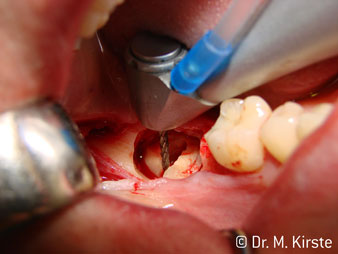

Elegir el ángulo de 45º ofrece múltiples ventajas de uso. Los odontólogos dedicados a cirugía (para quienes se desarrolló principalmente esta pieza de mano) se percatarán de inmediato de que se puede trabajar de forma muy específica. En especial en la remoción de las muelas del juicio (Fig. 2), no es necesaria una gran abducción de las partes blandas en la zona del carrillo (Fig. 3). El diseño del cabezal de la pieza de mano, combinado con los suaves giros del cabezal durante la preparación, permite trabajar de forma rápida y segura en la zona retromolar.

Acerca del trabajo rápido: puede conseguirse una velocidad de más de 100.000 rpm. Una refrigeración absolutamente profesional y un pequeño cabezal resuelven cualquier duda sobre los efectos térmicos o el trabajo con buena visibilidad.

El nuevo diseño de los rodamientos dentro del cabezal de la pieza de mano garantiza el funcionamiento silencioso de la fresa, en la separación del diente o la raíz (Fig. 4-9) se muestra una impresionante imagen de corte sin efectos de impacto.